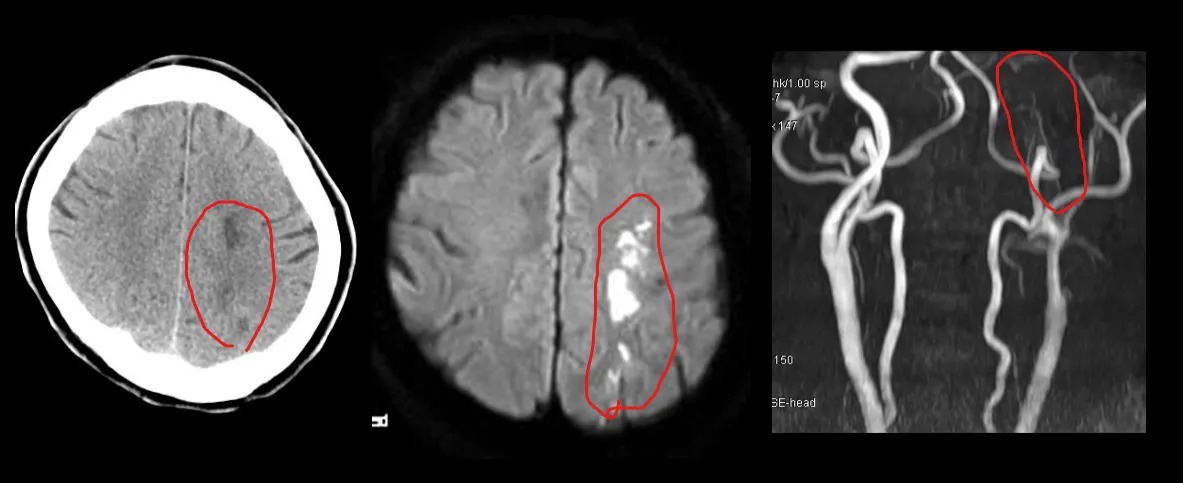

갑자기 우측 상지 마비가 발생하고 의식이 떨어진 환자. superior saggital sinus가 HU 80정도로 밝게 보인다. angio에서 이 병변은 thrombus로 확인되었다.

우측 centrum semiovale에 hypodense한 병변이 보이며, MRI에서 Rt MCA stenosis 가 관찰되었다.

좌측 centrum semiovale에 infarction이 보인다. MRI에서 동측의 ICA occlusion 이 발견되었다.